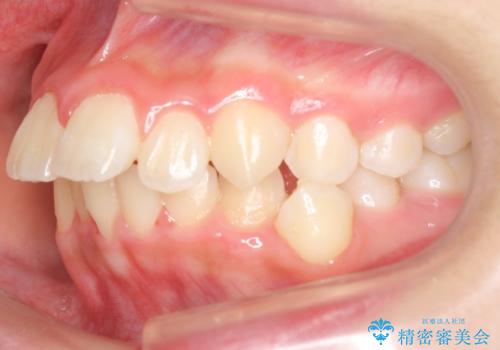

中学生のマウスピース矯正 歯を抜かずにキレイに

- 10代女子

- 矯正装置

- インビザライン フル

- 治療期間

- 1年11ヶ月

- 出っ歯を主訴に来院。

(1)インビザラインで歯を少し削って並べる。歯は抜かない。・・・歯を抜かなくて良い。歯磨きが楽、装置も目立たない。通院は3ヶ月に1回。

非抜歯ながらも、矯正用のインプラントを使用し、出来るだけ前歯を下げるように工夫して治療しました。

歯を抜かずに治療しましたが、治療前後で口元が悪化しないように治療することができました。